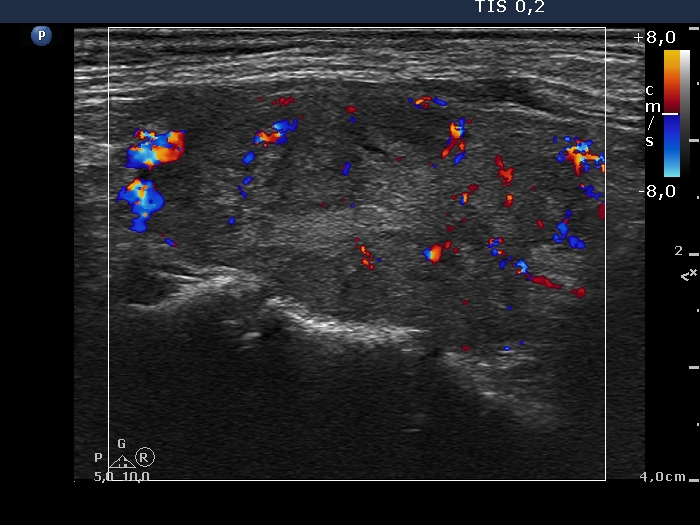

Second examination 6 years later (second row of images):

Clinical data: The patient was referred for a follow-up.

Palpation: unchanged.

Laboratory tests: TSH 3.52 mIU/L.

Ultrasonography. The pattern was the same as in the previous study except for the lesion in the isthmus which has been increased in size.

Suggestion: TSH in a year, ultrasound in 3 years.

Comment. This is the typical presentation of the micronodular form of Hashimoto's thyroiditis.